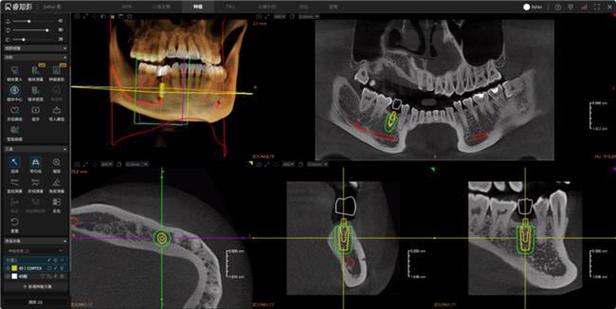

- 结果解读: 检查结果(X光片)会由专业的口腔颌面放射科医生或你的牙医进行解读,并据此制定诊断和治疗方案,患者通常无法自行看懂图像细节。